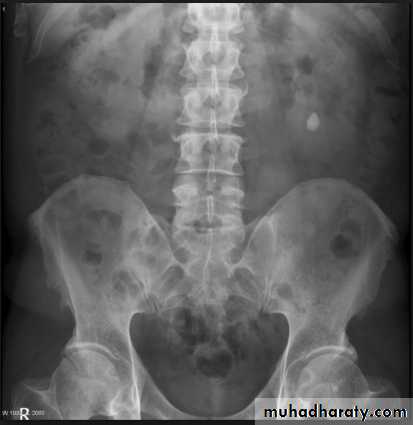

- Over 90% of calculi are radiopaque on plain films and virtually all on CT as very sensitive for detection of calculi, even those that appear radiolucent on plain film.- Most of these stones are a mixture of calcium oxalate and phosphate.

- Only pure uric acid and xanthine stones are radiolucent on plain x-ray but CAN be identified by CT or US , uric acid stones are associated with increased uric acid excretion in urine as in gout.

l.V.U. findings:

-Plain film may be useful in demonstrating calculi. -After contrast injection: Acutely obstructed kidney shows a dense nephrogram (dense opacification of the renal parenchyma).

Ddx of stone on KUB :

1. Gall stone2. Calcified LN , cartilage ,fibroid,

3. Phlebolith: round, lucent centre.